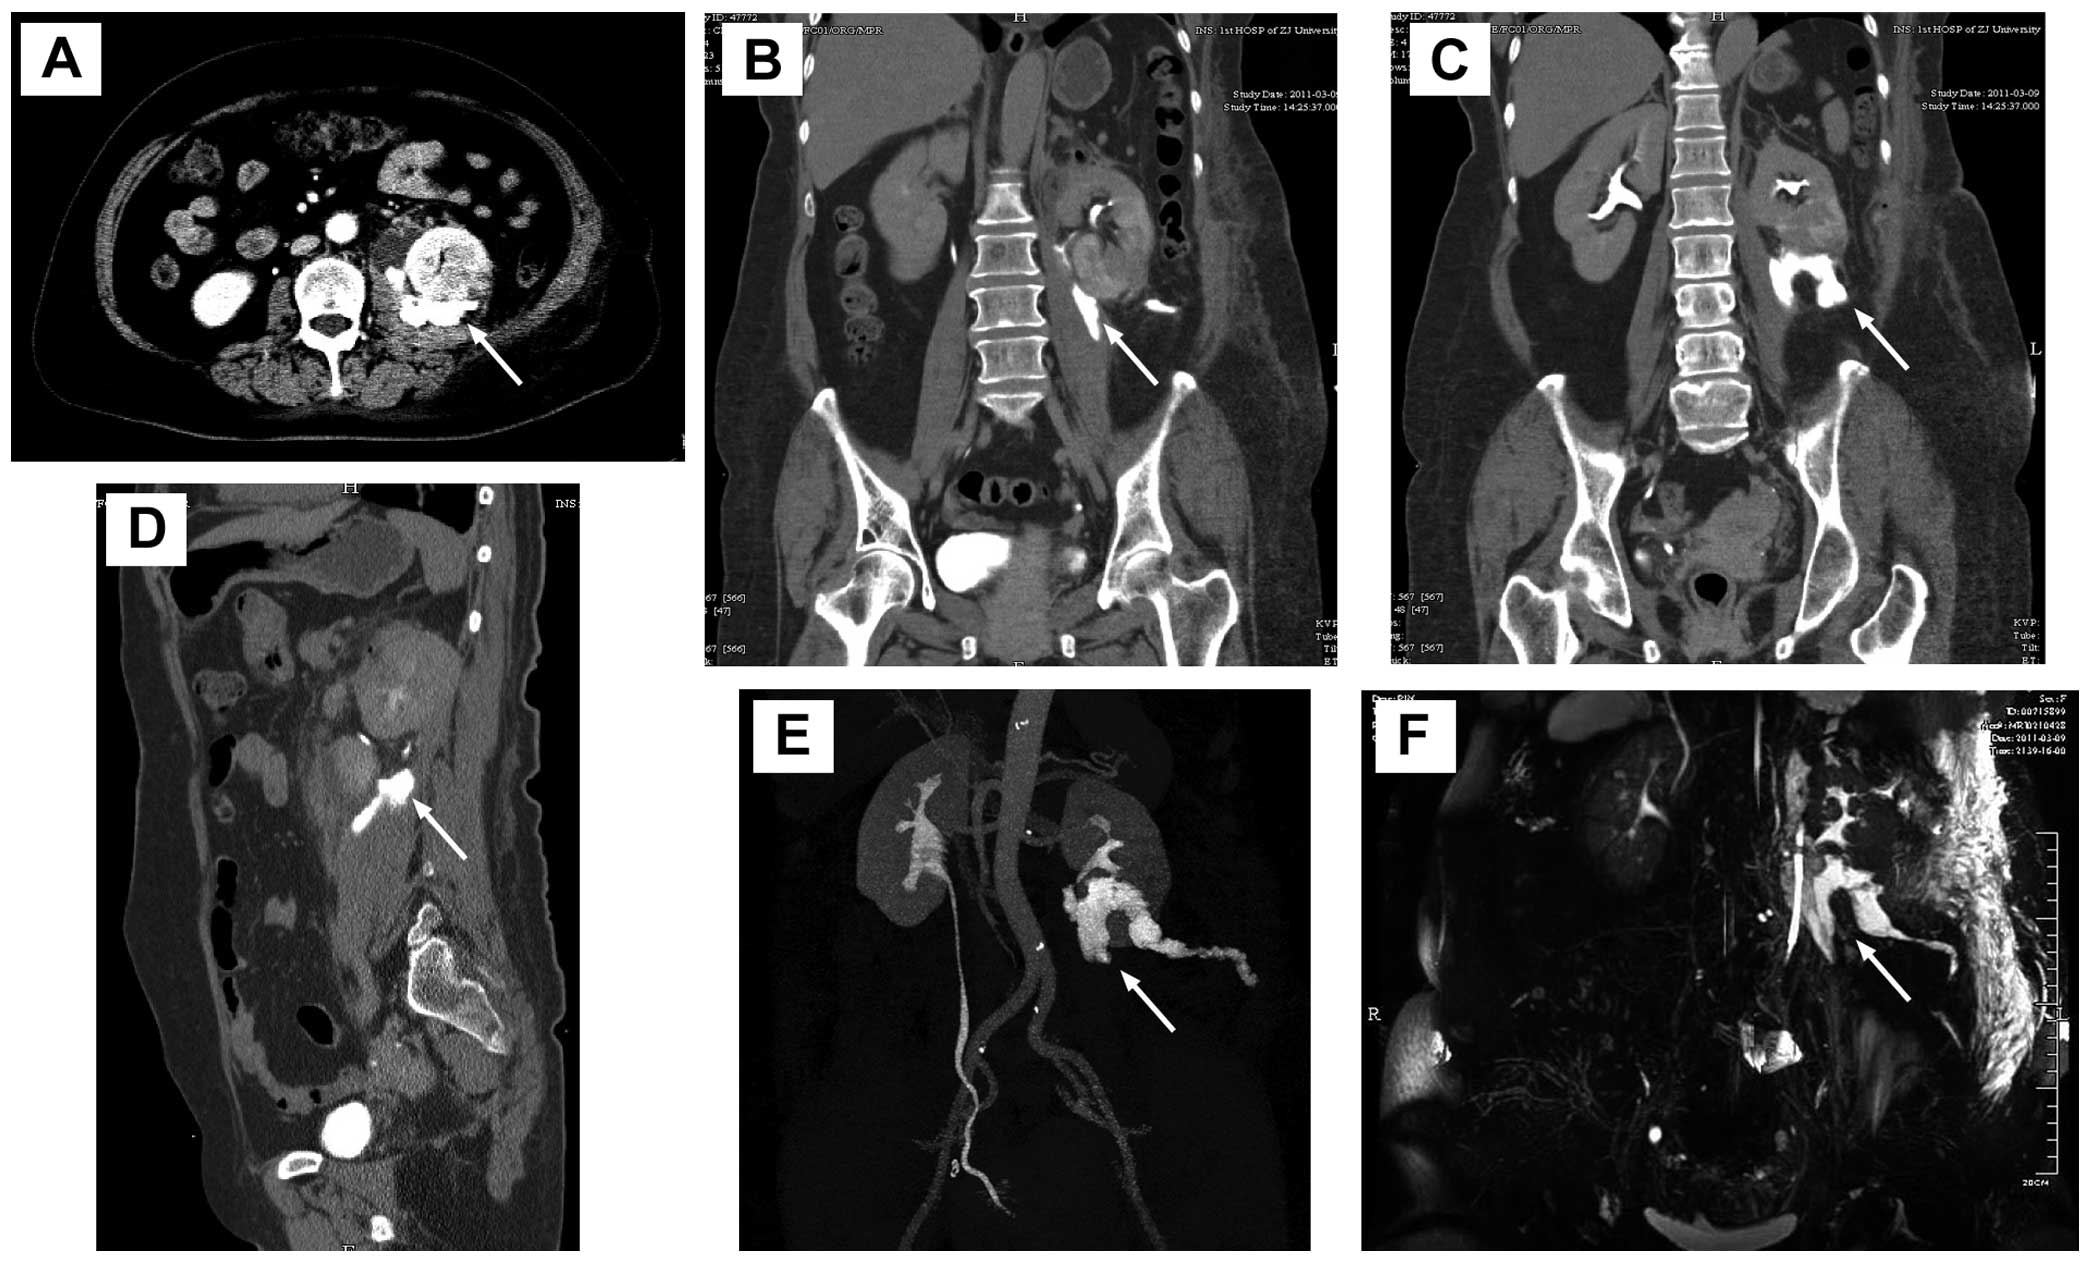

However, the patient was re-admitted on the 14th postoperative day due to the discharge of increasingly milky, thin, odourless fluid every day from the unclosed external orifice of the drainage tube. The amount of fluid reached 800 ml on the second day after re-admission. The creatinine concentrations of the fluid and urine were 1847 and 4640 μmol/l, respectively. The result of qualitative analysis of chyle was negative. CT urography (Fig. 2A–E) revealed a clear renal collecting system and no significant hydronephrosis. However, contrast remained in the left kidney and upper ureter and leakage in the perirenal space and along the psoas muscle, and was drained out of the body through the drainage tube. Moreover, no contrast agent was observed in the middle and lower ureter. In MR urography images (Fig. 2F), there was fluid signal in the perirenal space, particularly inside and below the left kidney. The results of CT and MR urography revealed left urinary fistula. A 5-F ureteral catheter was inserted into the left ureter for retrograde pyelography and elevated ∼20 cm but did not pass to the left renal pelvis. Then reoperation was performed on the 16th postoperative day to explore the left kidney and ureter in order to relieve the obstruction, allow unobstructed drainage and save renal function (Fig. 3). During the reoperation, almost complete occlusion of ureteral stricture was found in the upper ureter 5 cm from the left ureteropelvic junction. The ureter near the stricture was enfolded by fibrin glue and exhibited marked stiffness and adhesion. The lesion of the ureter was resected and the ureter was anastomosed end to end with the routine double-J stent (Fig. 4). Pathological examination of surgical specimens revealed fat fibrous scar tissue hyperplasia with inflammatory cell infiltration. The double-J tube was removed by cystoscopy two months after the second surgery. The patient recovered completely without exudate.

Figure 3

Reoperation was performed to explore the left kidney and ureter. (A) Almost complete occlusion of ureteral stricture was found in the upper ureter (arrow). (B) Surgical wounds of the left kidney (arrow) healed well. (C) The ureter was anastomosed end to end with the routine double-J stent (arrow).

Figure 4

Postoperative (A) CT and (B) plain abdominal X-ray showing the double-J tube (arrow) in the correct position.